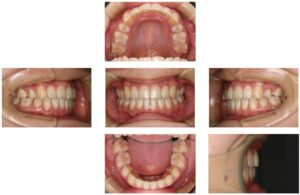

出っ歯の改善〔裏側矯正・福岡・天神〕

| 主訴 | 前歯が出ている |

| 診断 | 叢生 |

| 治療内容 | フルリンガルブラケット |

| 上顎左右4、下顎左右5抜歯 | |

| 治療期間 | 2年10か月 |

| 費用 | 1,150,000円 |